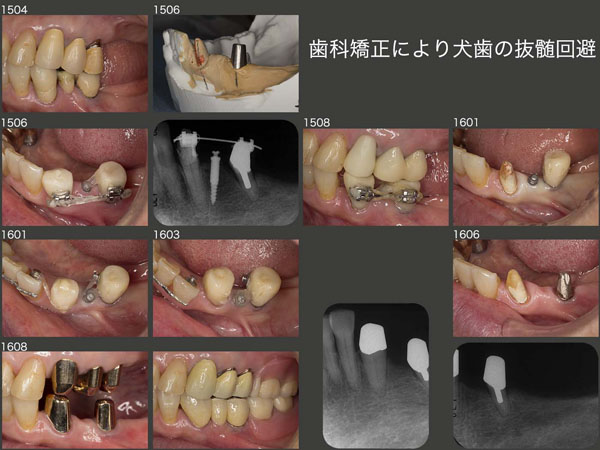

4.歯科矯正により犬歯の抜髄回避

右下にはインプラントが装着されており,長い間自分の歯が上下にある左側ばかりで咀嚼していた.そのためか,左上4,5の歯の動揺が増し,連結固定が必要になった.また,左下3にも2次カリエスが生じ,左下ブリッジの再製作も必要になったので,この際左側の上下顎にコーヌス義歯を製作することにした.ここでは特に,左下3が前方に傾斜していることが問題となった.

スライド上段の模型の赤塗り部分を削去すればよいのだが,そうなると抜髄は必須である.将来左下5を失うことがあっても,左下3が有髄歯のまま保存できていれば,十分義歯で対応できる.そこで何としても左下3を抜髄することは避けたかった.まず2015年6月,ミニインプラントを固定源に用いることで,遠心方向へのアップライトを開始した.8月,遠心へのアップライトは完了し,暫く保定した.

ところが,16年1月,暫間被覆冠を外してみると今度は頰側に傾斜しているのに気が付いた.そこでもう一度,舌側に傾斜移動を行った.3月,舌側への移動が終了した.私の拙い治療で治療期間が長くなってしまい,本当に申し訳ないと思う.

8月,左下3を抜髄することなしに,コーヌス義歯を装着することができた.21年3月時点では,特に問題ない.